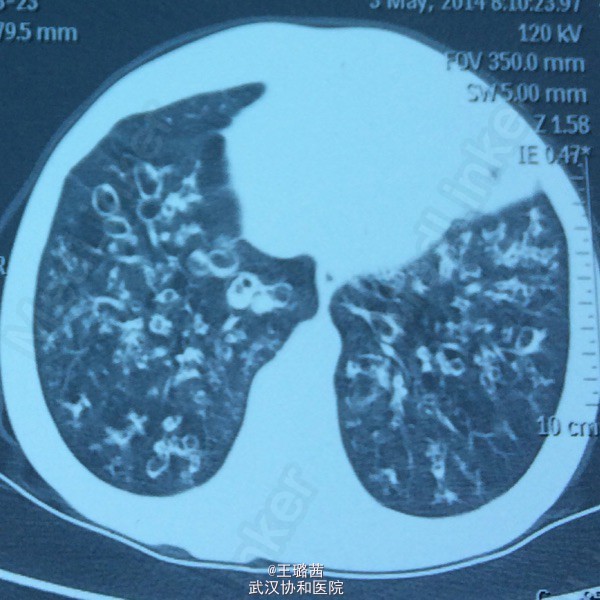

支气管扩张

女,48岁。反复咳嗽咳痰十余年,再发加重十余天。